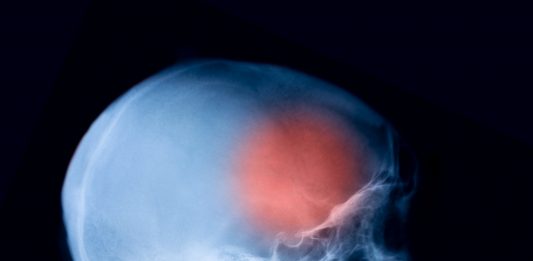

POTSDAM. Meningokokken sind selten, aber lebensgefährlich. Der Tod eines siebenjährigen Schülers in Potsdam schockt und beunruhigt Eltern und Lehrkräfte. Warum schnelles Handeln bei einer Infektion mit Meningokokken zählt. Nach dem Tod eines Siebenjährigen an einer Meningokokken-Infektion hat die Stadt Potsdam eine Vorsorgeaktion zum Schutz vor weiteren Ansteckungen fortgesetzt und klärt Verdachtsfälle ab. Meningokokken-Erkrankungen sind selten … Grundschüler stirbt an Meningokokken-Infektion – Kontaktpersonen in Behandlung weiterlesen